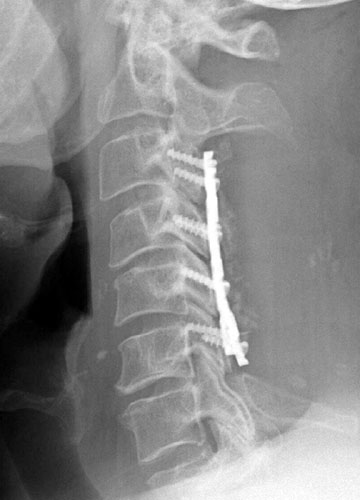

AP and lateral radiographs taken 5 days after surgery demonstrate

typical laminectomy defects at C3-6. The posterolateral fusions appear intact

with bone grafting material faintly appreciated. The screws and plates are

intact and in appropriate positioning. |